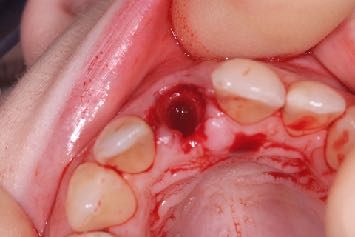

Plus important encore, on lit fréquemment que, pour augmenter artificiellement ce couple, il faudrait pratiquer une plus petite ostéotomie ou recourir à des techniques de compression osseuse. Or on dispose de plusieurs exemples dans la littérature qui prouvent que ces pratiques sont préjudiciables à la cicatrisation, risquent d’endommager l’os et de retarder le processus d’ostéo-intégration.

Il faudrait se concentrer sur la stabilité secondaire et l’obtenir le plus vite possible, en préservant en même temps la viabilité et la stabilité de l’os péri-implantaire, pour assurer la réussite clinique de l'implant à long terme.

Je suis convaincu que le maintien de l’os marginal péri-implantaire est l’un des facteurs clés de prévention des complications biologiques futures. Par conséquent, si l'on arrive à obtenir une stabilité secondaire en minimisant les lésions osseuses au niveau cellulaire, les conditions d’une réussite prévisible durable sont presque entièrement remplies.